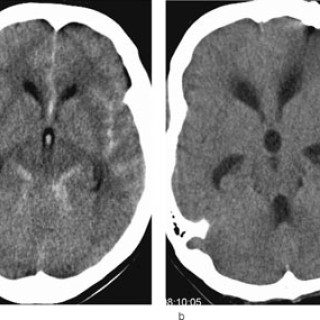

Den første detaljerte beskrivelsen av cerebral venetrombose, også kalt sinusvenetrombose, ble forfattet av Ribes i en artikkel fra 1825 (1). Siden fulgte en rekke kasuistikker basert på autopsimaterialer, som førte til den oppfatning at cerebral venetrombose representerte en sjelden, alvorlig sykdom karakterisert med hodepine, papillødem, epileptiske anfall, fokale utfall, progredierende koma og død (2, 3). Introduksjon av moderne nevroradiologisk utredning har gjort diagnostisering intra vitam mulig, dermed er det blitt klart at sykdomsutviklingen ved cerebral venetrombose heller sjelden er i...